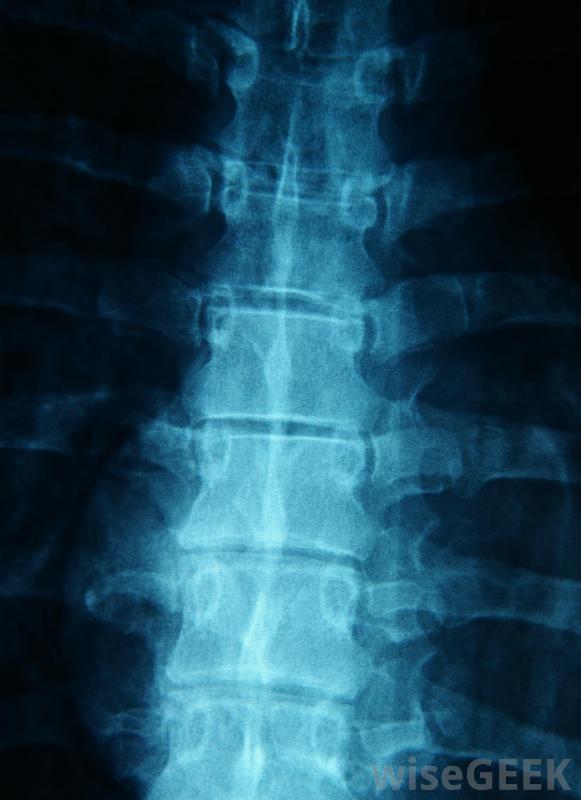

坐骨神经痛是一种非常痛苦的疾病,在孕妇中尤为常见。许多孕妇和其他患有坐骨神经痛的孕妇考虑接受脊椎按摩治疗,因为它是非侵入性的,非手术性的被许多不同的团体讨论过,很明显,脊椎指压师相信他们的治疗方法对缓解和矫正坐骨神经痛是有效的。大多数脊椎指压师都会使用X光检查脊柱的总体健康状况脊椎指压疗法对于那些寻求减轻疼痛和纠正由坐骨神经痛引起的问题的人来说是一个很好的选择。脊椎指压师可以在不咨询的情况下诊断和评估坐骨神经痛骨科医生,他们对这种情况的治疗就像对待任何其他由脊柱错位引起的问题一样:治疗过程是基于定期调整脊柱。然后椎骨将重新排列并减压,使脊柱周围的肌肉正常工作,最终减少挤压脊柱的肌肉的张力坐骨神经。总的目标是减轻神经的挤压,消除周围肌肉的过度压力。某些类型的按摩可能对坐骨神经痛的治疗有用坐骨神经是人体最大的神经之一,这也是坐骨神经痛如此痛苦的原因之一,有时需要多次按摩治疗才能获得缓解。在决定是否尝试脊椎按摩治疗坐骨神经痛时,个人应意识到脊椎指压师喜欢找到调整患者脊柱前的问题。大多数脊椎指压师使用X射线或磁共振成像(MRI)技术来检查脊柱的曲线、组成和一般健康状况。考虑到脊椎按摩的自然、无创、非手术方法,它可以通过一两次探视来确定问题所在和正确的治疗过程。脊椎按摩的实践中心是脊椎的调整和调整,然而,许多脊医在治疗坐骨神经痛时使用电刺激设备来促进愈合过程。电刺激对坐骨神经痛的治疗尤其有效,因为它可以减少肌肉痉挛、神经刺激和炎症。一些脊医在使用脊椎按摩疗法时也会与按摩治疗师合作对于坐骨神经痛的治疗。这种辅助疗法有助于靶向肌肉更快地愈合。坐骨神经痛是一种常见病。人们是否可以通过脊椎按摩治疗坐骨神经痛的问题一直在争论医学界的不同团体。虽然这场争论仍未解决,但成千上万的人,特别是孕妇,已经寻求脊椎按摩疗法来解决他们的坐骨神经痛问题如果坐骨神经受到刺激,会导致腿部疼痛和麻木。